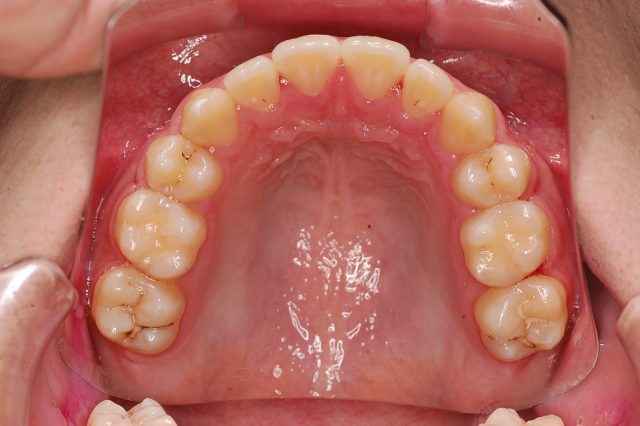

Before

After

主訴

前歯で噛めない

治療期間・回数

2年6ヶ月・30回

治療方法

マルチブラケットにて上下左右4本抜歯

費用

850000+税

デメリット・注意点

歯根吸収 歯肉退縮